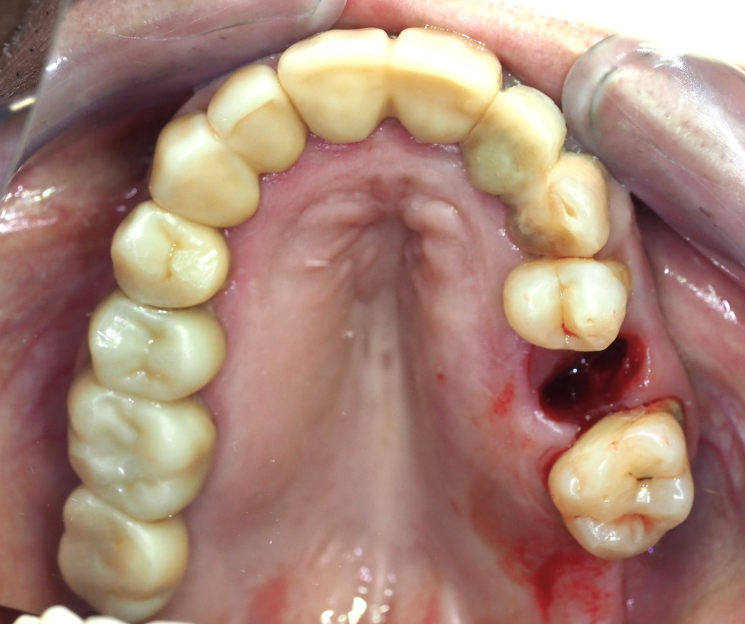

- Extracción atraumática: Se realizó la exodoncia del diente 25, preservando al máximo las estructuras óseas.

- Colocación del implante: Se procedió a la inserción del implante monofásico compresivo en el mismo acto quirúrgico.

- Estabilidad: Gracias a la condensación ósea lograda, se obtuvo una fijación óptima que permitió la carga inmediata.